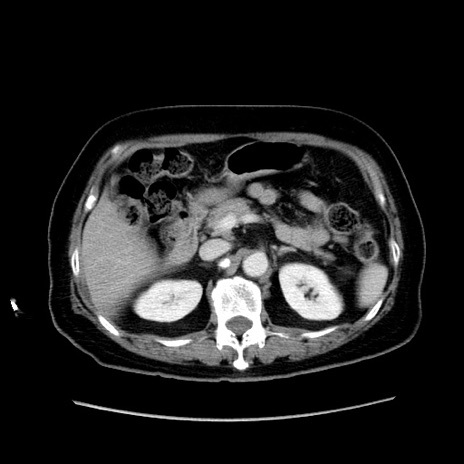

症例19(横断像)

【症例】80歳代女性

【主訴】下腹部痛

【現病歴】約8時間前より下腹部痛の出現あり、救急外来受診。

【既往歴】両側付属器切除

【身体所見】意識清明、下腹部正中に手術痕あり、その部位に一致して圧痛と反跳痛あり。腸蠕動音は亢進。

【データ】WBC 9300、CRP 0.15